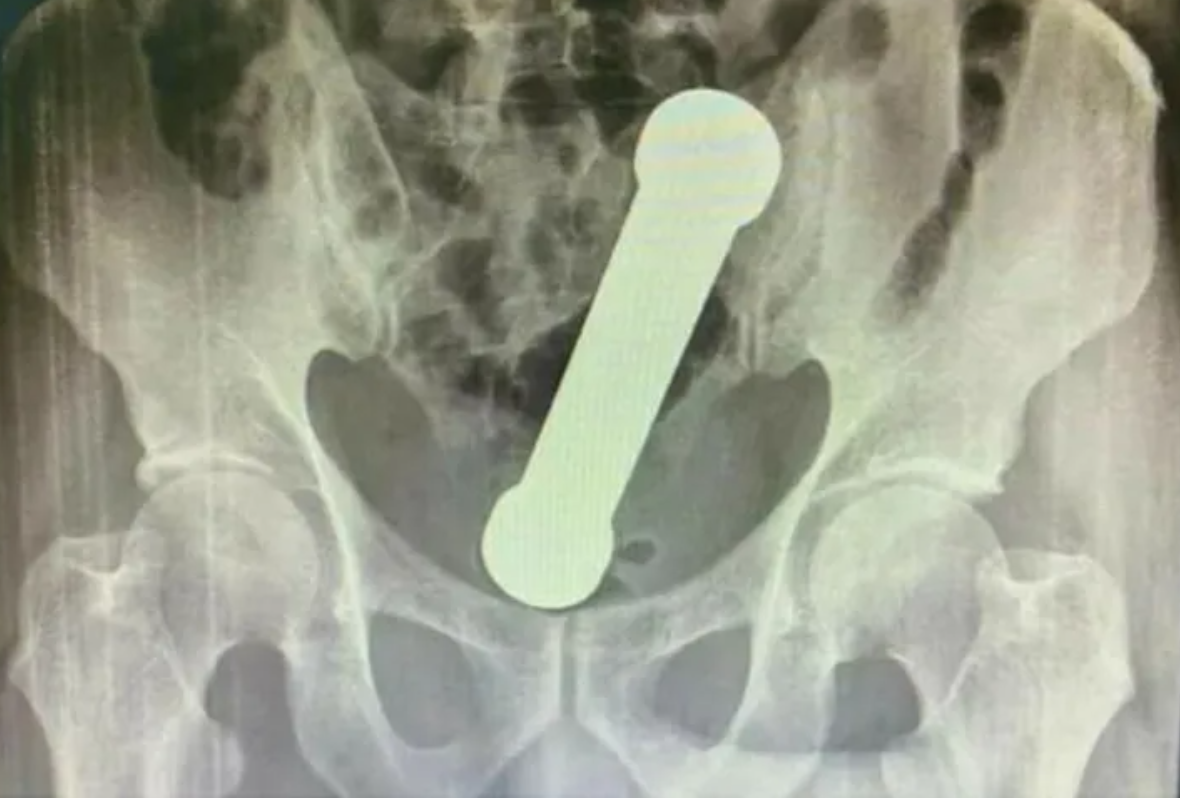

Os médicos encontraram o peso de dois quilos, de cerca de 20 centímetros de comprimento, como os que são usados em academias de ginástica para exercícios de braço, ao realizarem um exame de raio-X. O halter estava entre o reto e o intestino grosso do paciente.